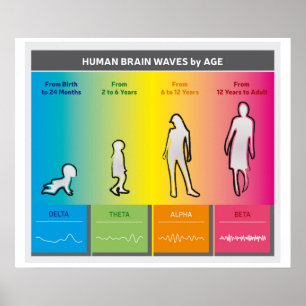

Diagrama das ondas do cérebro humano - Poster das

Preço38,10 €